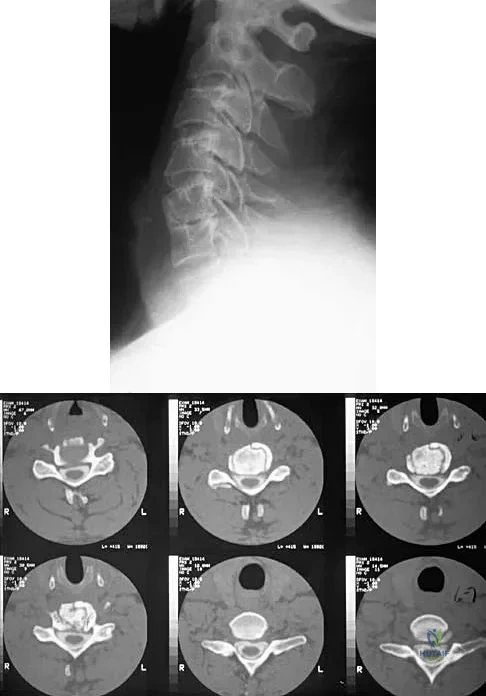

A patient underwent an anterior cervical diskectomy and interbody fusion for a C5-6 herniated nucleus pulposus and left C6 radiculopathy 8 months ago. He now reports new onset of severe neck pain and left C6 radicular pain, with wrist extension weakness. The radiograph and CT scan shown in Figures 26a and 26b reveal pseudarthrosis at C5-6. The next step in management should consist of